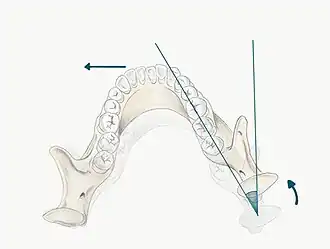

The maxilla forms a crucial aspect of the upper facial skeleton. Two irregularly shaped bones fuse at the intermaxillary suture during development forming the upper jaw. This forms the palate of the oral cavity and also supports the alveolar ridges that hold the upper teeth in place.[3] The lower facial skeleton on the other hand, is formed of the mandible, a U-shaped bone, which supports the lower teeth and also forms part of the TMJ. The mandibular condyle and the squamous portion of the temporal bone, at the base of the cranium articulate with one another.[4]

When the mandible is in this retruded position, it opens and closes on an arc of curvature around an imaginary axis drawn through the centre of the head of both condyles. This imaginary axis is termed the terminal hinge axis. The first tooth contact that occurs when the mandible closes in the terminal hinge axis position, is termed Retruded Contact Position (RCP).[13] RCP can be reproduced within 0.08mm of accuracy due to the non-elastic TMJ capsule and restriction by the capsular ligaments, thus it can be considered a ‘border movement’ in Posselt’s envelope.[14]

Posselt’s Envelope of Border Movement (often referred to as the 'border movements of the mandible') is a schematic diagram of the maximum jaw movement in three planes (sagittal, horizontal and frontal). This encompasses all movements away from RCP, and includes:

- Protrusive movements: When the mandible moves forward from centric relation, this is considered as protrusion.[12] In Class I occlusion, the predominant contacts occur on the incisal and labial surfaces of the mandibular incisors and the incisal edges and palatal fossa areas of the maxillary incisors.[6]

- Lateral movements: When the mandible moves to the left or right, the mandibular posterior teeth move laterally across the opposing teeth. For example, when the mandible moves to the right, the right mandibular teeth move laterally across their opponents and this is termed the working side of the mandible (the side towards which the mandible is moving). In contrast, the left mandibular teeth move medially, downwards and anteriorly across their opposing posteriors and this is called the non-working side (the side to which the mandible is moving away from).

- Retrusive movements: This is when the mandible moves posteriorly from ICP. Compared with protrusive and lateral movements, retrusive movements are generally considerably smaller with a range of movement around 1 or 2 mm due to restriction by the ligamentous structures.[2]